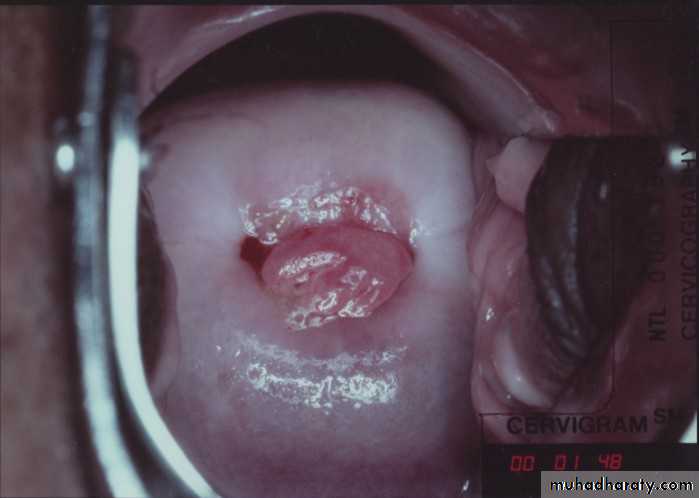

*Postcoital bleeding: is non-menstrual bleeding that occurs immediately after sexual intercourse.

cervicitis.

Cervical carcinoma.

Speculum examination: for cervix and vagina

Bimanual palpation to assess for uterine or adenexal enlargement or tenderness.